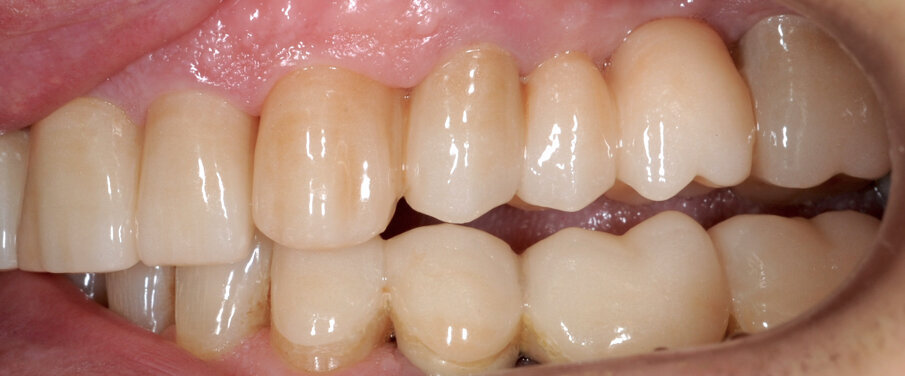

Il fresato ottenuto è poi riportato su articolatore Reference SL – già opportunamente programmato – e viene dall’Odontotecnico competente più precisamente funzionalizzato secondo i criteri della programmazione funzionale sequenziale, evidenziando con cere colorate i rapporti di centrica, le funzioni di mediotrusiva e protrusiva e le protezioni retrusive. I monconi sfilabili consentono la modellazione della sequenzialità mediotrusiva con la guida incisale indicata dalla registrazione axiografica (blu) (Figg. 34-37). La ceratura sequenziale è ora scansita con Sirona InEos X5 su Exocad, ed il modellato viene ricontrollato al CAD per spessori, connessioni e morfologia, e nella regolazione degli offsets per la ripreparazione dei monconi, ed è inviato al CAM per la fresatura dei II provvisori in Bredent breCAM.multicom, un PMMA con microriempitivo ceramico ad alta stabilità, su Dental Plus 5 Axis Milling Machine. La rifinitura dei monconi è seguita da ribasatura dei II provvisori in TRP - previo isolamento di tutte le superfici funzionali - e gli stessi sono poi rifiniti e lucidati. I soli elementi 3.3, 4.2 e 4.3 sono rimodellati in regione incisale con addictions in composito, secondo la morfologia studiata in ceratura. La consegna conferma la buona integrazione dei manufatti dal punto di vista estetico, occlusale, articolare e neuromuscolare, con controllo occlusale conforme al progetto (Figg. 38-42).

Il paziente utilizza questi secondi provvisori per otto settimane, durante le quali conferma la buona integrazione dei restauri e la soddisfacente funzione occlusale. Ciò è verificato con l’esecuzione di una nuova axiografia elettronica che già a due settimane dalla consegna evidenzia una buona risposta muscolare al nuovo design occlusale ed alla nuova postura mandibolare in TRP (Figg. 43-46). Provvediamo infine alle impronte per la costruzione dei manufatti definitivi in Zirconia-ceramica. I modelli sono scansiti in laboratorio con inEos X5 (Dentsply Sirona) su exocad (Figg. 47-49), ed una seconda scansione viene eseguita con i provvisori del Paziente posizionati sui modelli (Figg. 50-52). Il CAD consente di eseguire un matching fra le due scansioni, per cui i secondi provvisori utilizzati in TRP, con funzione occlusale sequenziale già completamente programmata, sono utilizzati per definire le morfologie dentali definitive di tutti gli elementi da restaurare (Figg. 53, 54) secondo il rapporto intermascellare definito (Figg. 55-58). Si esegue quindi fresatura al CAM della protesi definitiva in zirconia (Figg. 59, 60), la stratificazione e finitura ed infine la consegna al Paziente con cementazione in Panavia V5 (Figg. 61-65).